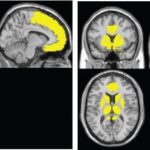

Study: Novel brain map tracks early brain atrophy from HIV infection — (Details)

A new map of brain tissue in people with HIV shows atrophy in several areas including a primary neurocognitive control center where shrinkage...